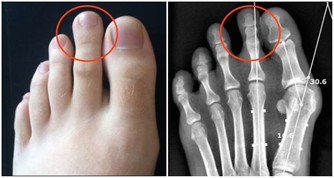

實驗證明,大白菜所含有的許多物質、具有防癌抗癌的作用,因此在美國國立癌癥研究所、發表的防癌食品排行榜中、將白菜排在僅次於大蒜的後面,名列第二。。

首先,大白菜中含有豐富的維生素A和維生素C,其中維生素C的含量比黃瓜高4倍、比番茄高1.4倍;維生素A的含量,比黃瓜高1.8倍。

維生素C也叫抗壞血酸,能夠阻止致癌物質亞硝胺的生成,同時能抑製癌細胞的增殖。

其次,大白菜含有一種叫做吲哚-3-甲醇的化合物,其含量約佔大白菜重量的0.01%,它能促進人體產生一種重要的酶,這種酶能夠有效抑製癌細胞的生長和分裂。

另外大白菜所含有的微量元素鉬~是人體金屬酶的重要組成部分,據調查在食道癌的高發地區,人們頭發當中鉬的含量最低,這與當地水土中缺鉬是有關的。

能夠防止致癌物亞硝銨合成的微量元素鉬、大量存在於大白菜中,能阻斷亞硝胺等致癌物質在人體內的生成,所以能防止癌癥的發生。

據測算,每天吃1磅大白菜,或白菜榨汁,每天飯後服200-300克,就能吸收到500毫克這種化合物,達到預防癌癥的目的。